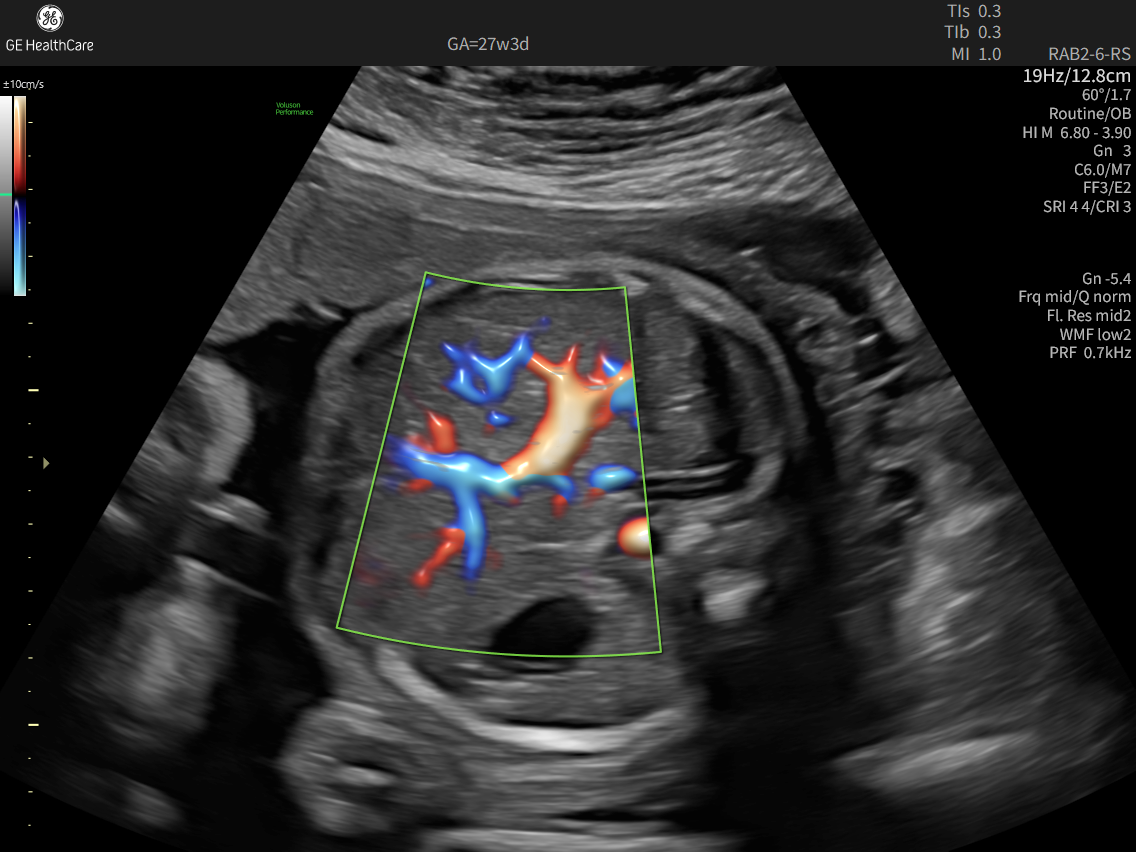

Fast, easy 3D-like blood flow visualization

Go with the flow